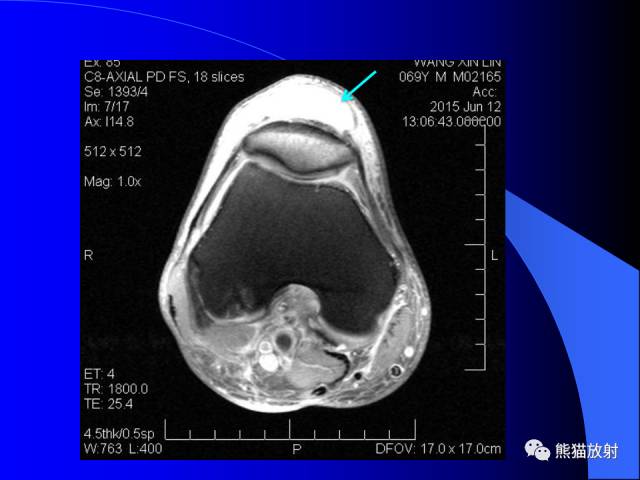

膝关节周围囊肿是较常见的病变,可以是原发的,多见于青年及儿童,囊内容物通常是黏液;也可以是继发的,多与关节腔相通,内含一般黏性的滑液,常继发于膝关节骨关节炎、类风湿关节炎、非特异性滑膜炎、半月板损伤、髌骨软骨软化症等。

以上滑囊出现炎症时均可形成滑囊囊肿。